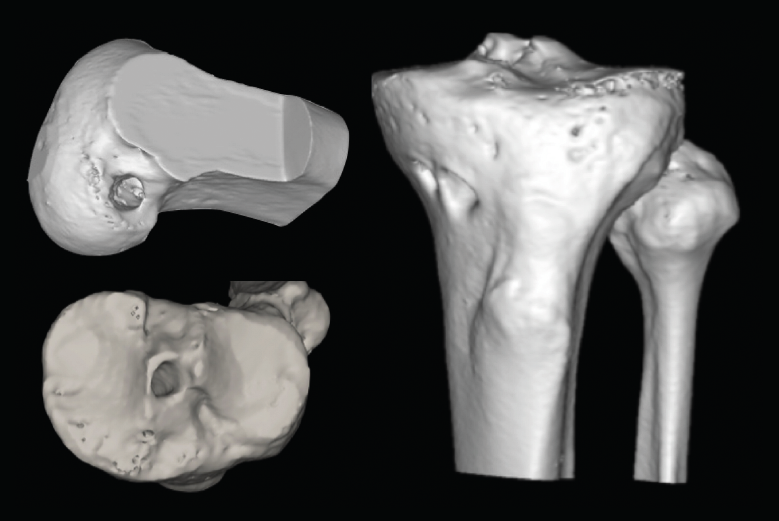

El estudio mediante TC, tanto en 2D como en las reconstrucciones actuales en 3D, va a ser de gran utilidad para poder identificar la posición de los túneles óseos tibial y femoral, la dirección de ambos y, finalmente, el grado de dilatación y la morfología de los mismos. Estos aspectos van a ser claves para poder planificar la cirugía de revisión en uno o dos tiempos (Figuras 3 y 4).

Figura 3. La tomografía computarizada en 2D mediante cortes axiales, coronales y sagitales permite conocer tanto la dirección como la morfología de los túneles previos, así como medir el grado de dilatación de los mismos para planificar la cirugía de revisión.

Figura 4. Actualmente, la reconstrucción en 3D de la tomografía computarizada permite comprender mejor la localización tridimensional de los túneles óseos.